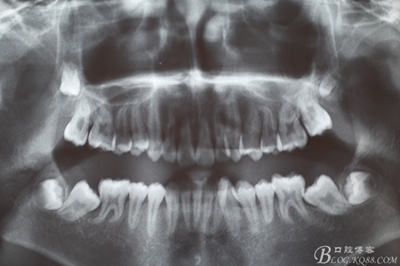

圖1.術(shù)前患者的全景片檢查:38、48牙冠已經(jīng)形成,牙冠方向為水平位,37、38近中位萌出。